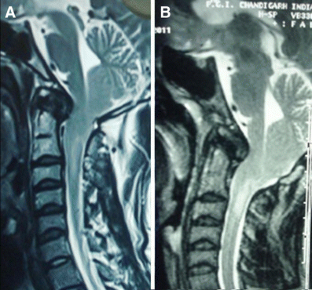

Sixteen adult patients with Chiari I malformation with significant ventral cervicomedullary compression, in the absence of BI, were included in the study. Atlantoaxial dislocation (AAD) was excluded in these patients by flexion-extension craniovertebral junction X-rays and computed tomography (CT). Their clinical profile, especially symptoms pertaining to cervicomedullary compression, i.e. dysphagia, dysarthria and spasticity, were graded. The ventral cervicomedullary compression (VCMC) was quantified using pBC2 (maximum perpendicular distance to the basion-infero posterior point of the C2 body) on sagittal magnetic resonance imaging (MRI) and only those patients with pBC2 ≥9 mm were included. Furthermore, retroversion of dens and retro odonotid tissue thickness was calculated in each patient. Fifteen patients underwent posterior decompression alone and one refused surgery. Follow-up was done every 3 months. Repeat MRI was done at 1 year following surgery to look for pBC2.

The mean pBC2 was 11 ± 0.2 mm. Retroversion of dens was responsible for VCMC in three patients and periodontoid crown in 13. There was no correlation between the tonsillar descent, age and the pBC2. All patients improved in symptoms of cervicomedullary compression following surgery. One patient worsened 6 months after initial improvement. The pBC2 did not change, as seen on follow-up MRI done in five patients.

VCMC in adult patients with Chiari I malformation in the absence of BI and/or AAD is due to periodontoid tissue (crown) or retroverted dens. Though a long-term study is required, it appears that all patients with Chiari I malformation, irrespective of the VCMC, can be given a chance with posterior decompression alone. Transoral decompression with posterior fusion may be required in a small subset of patients who fail to improve or worsen following posterior decompression only.